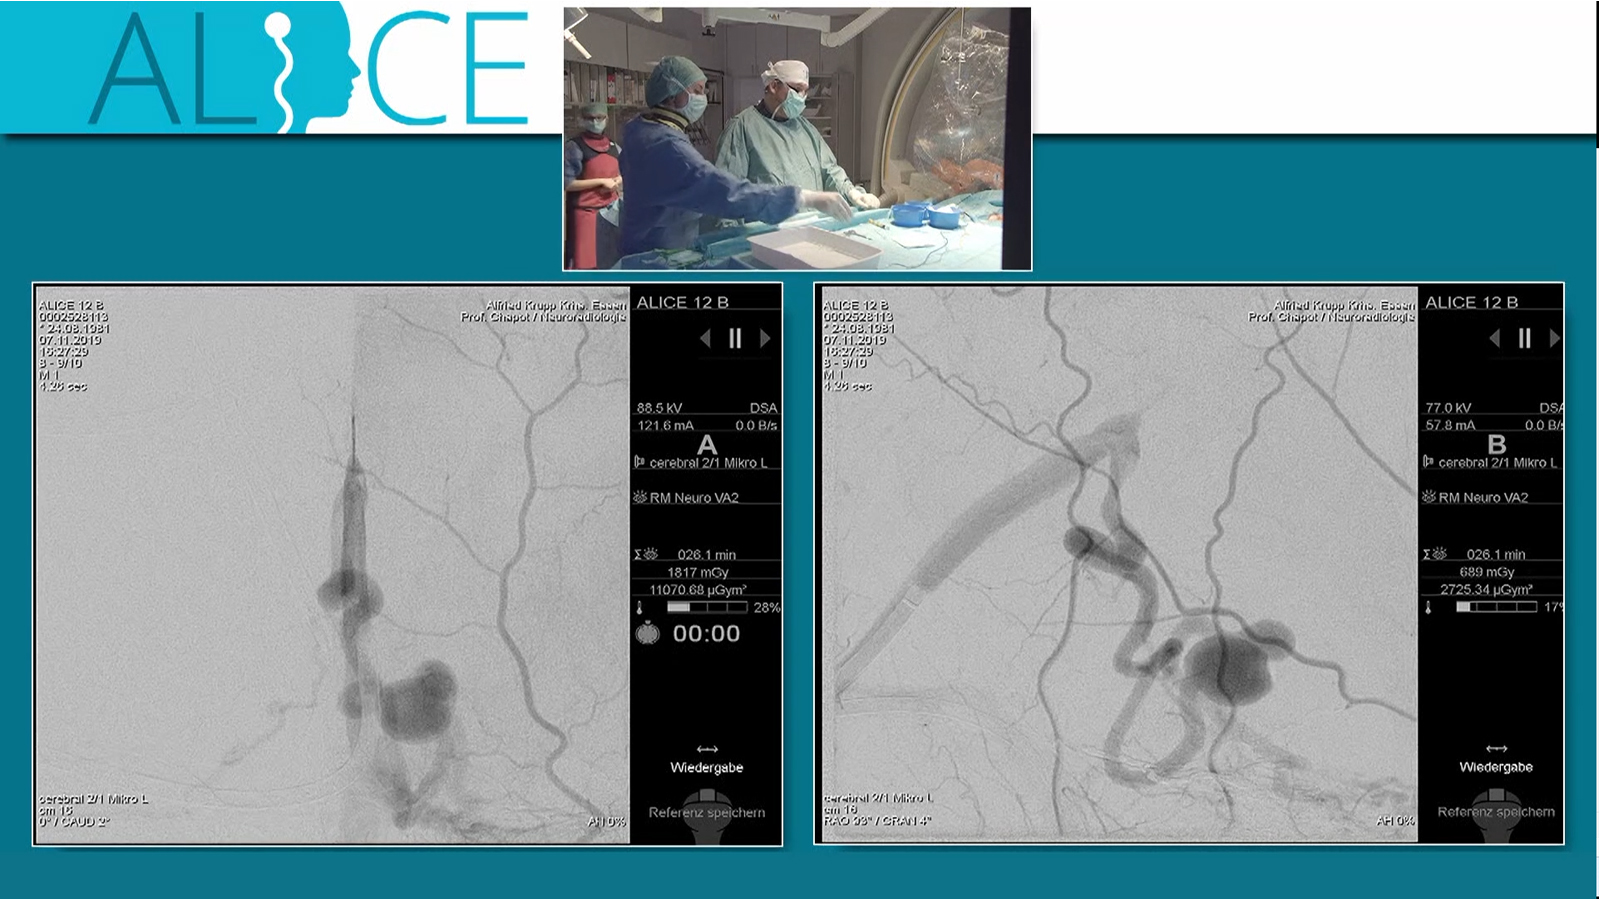

MCA aneurysm treated by double balloon assisted coiling followed by Stenting with Baby Leo

Watch the video

MCA Aneurysm treated by double balloon assisted coiling and Stenting with Baby Leo